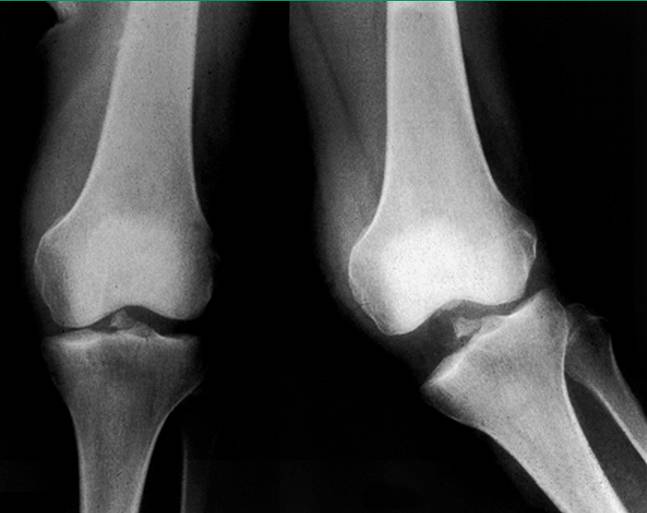

有些患者进行膝关节通道位摄片(Tunnel Radiograph of Knee)也有一定帮助。应力下摄片可帮助确定关节间隙的开放程度,尤其是内侧副韧带III级损伤患者或膝关节多韧带损伤的患者(图4)。

图4,应力下摄片显示内侧副韧带、前交叉韧带与后交叉韧带完全断裂